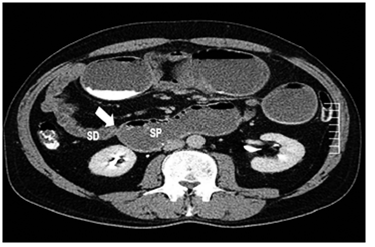

Por esta sintomatología, se le practicó una TC abdómino-pélvica con contraste una semana antes en otra institución, en la cual se informó dilatación de la cámara gástrica, duodeno y yeyuno proximal, con cambio de calibre abrupto a ese nivel, sin evidencia de otros hallazgos (figuras 1 y 2).

Fuente: Servicio de Radiología, Centro Médico del Caribe, Panamá

Figura 1. TC Abdomino pélvico en fase con contraste, corte axial a nivel de estómago y duodeno: dilatación de la cámara gástrica y del yeyuno.

Flecha: estrechez en el yeyuno proximal

SP: segmento proximal a la lesión

SD: segmento distal a la lesión

Figura 2. TC Abdomino pélvico en fase de contraste, corte axial.